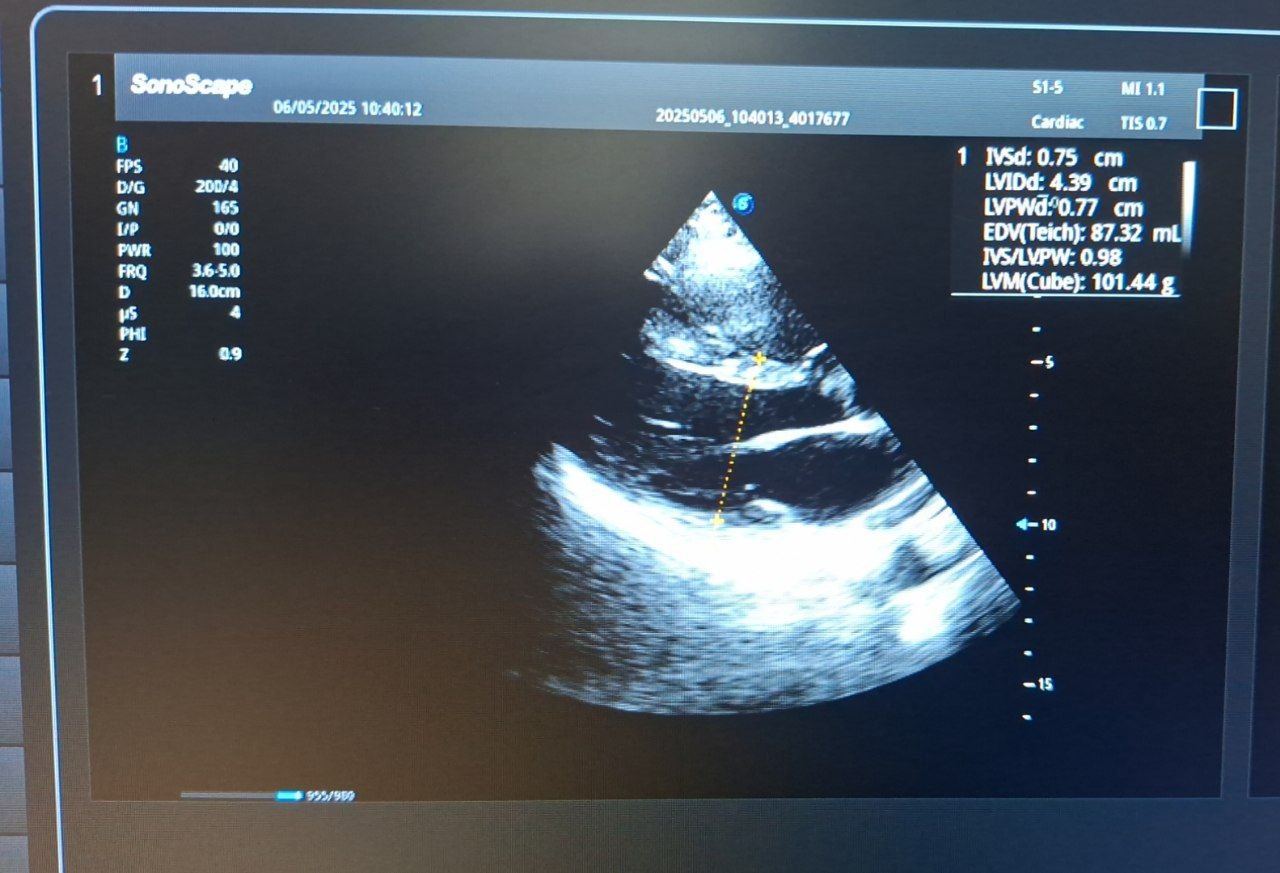

ЭхоКГ: Незначительная дилатация (расширение) корня аорты. Полости сердца не расширены. Гипертрофии миокарда ЛЖ нет.

Ключевая находка: Нарушение локальной сократимости миокарда ЛЖ в виде акинеза (06.05.2025) и гипокинеза (17.12.2025) передне-перегородочного среднего и верхушечного сегментов, что соответствует данным МРТ об аневризме верхушки. Фракция выброса ЛЖ: 57% (01.2025) -> 63% (05.2025) -> 68% (12.2025) – положительная динамика. Признаки легкой митральной и трикуспидальной регургитации (недостаточности клапанов 1 ст.).

Давление в легочной артерии в норме. Перикардиального выпота нет.